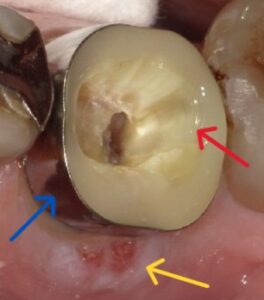

現状 左下7番の頬側に歯肉膿瘍を形成、遠心側に亀裂が見られる。ポケットは頬側に8ミリ計測できる。自発痛はないが咬合痛がある。

【黄色矢印が歯肉膿瘍 赤矢印が亀裂】

【赤矢印 亀裂 黄矢印 歯肉膿瘍】

亀裂がこれ以上拡大すると歯牙の保存が難しくなる可能性があるので、矯正用バンドで隔壁を兼ねて作成。遠心の亀裂もセメントで封鎖。

【青矢印 矯正用バンド 黄矢印 歯肉膿瘍 赤矢印 亀裂封鎖したセメント】